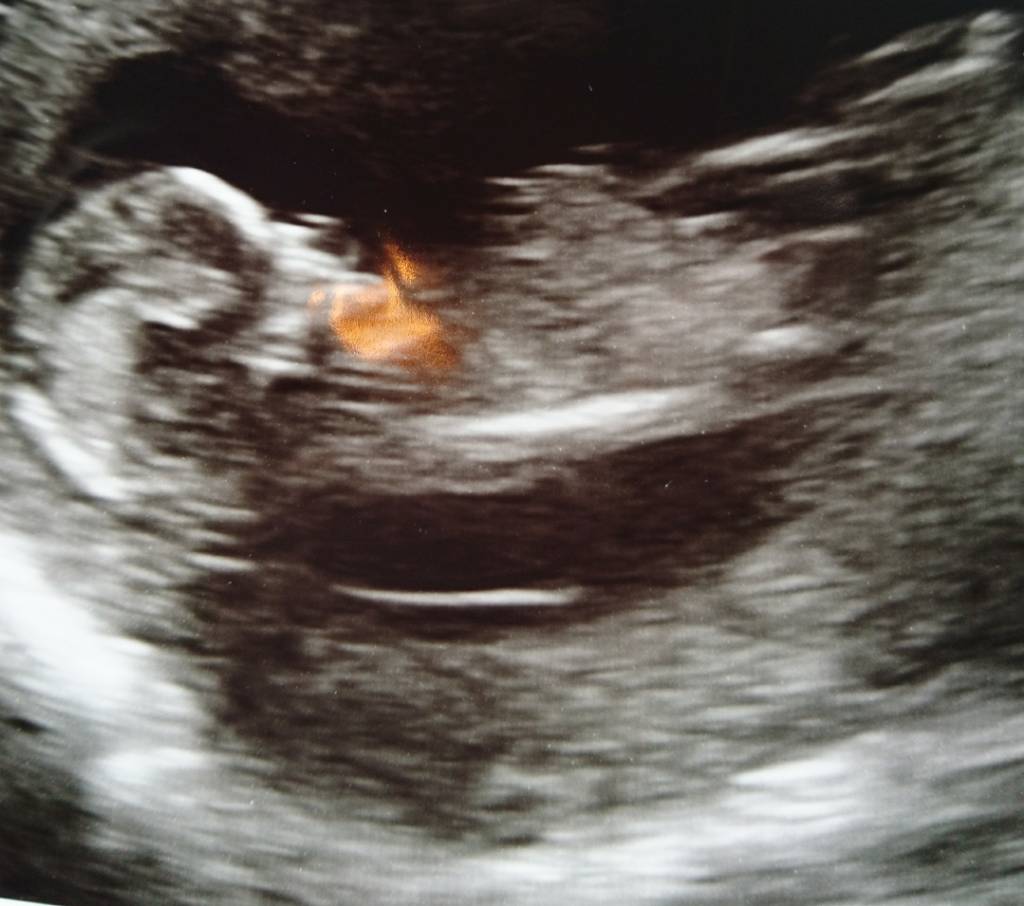

Tech was leaning pink... Thoughts???? Attachment 37718Attachment 37719

If what I'm seeing is the nub, I think boy. It looks really angled up.

I think I'd have to go boy [emoji170]on this one too